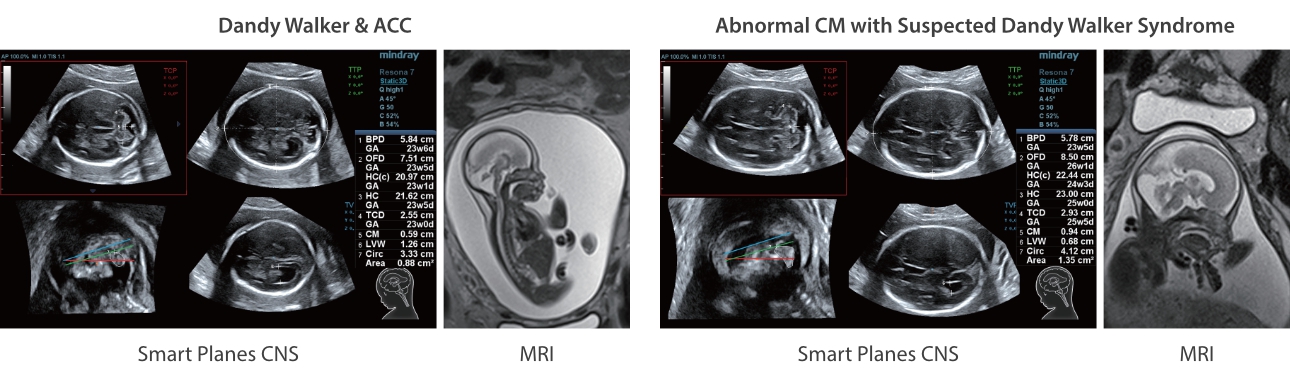

As well as the premium level image quality, Resona 7 also enhances clinical research capabilities with the revolutionary V Flow for vascular hemodynamic evaluation, and the most intelligent plane acquisition from 3D datasets for fetal CNS diagnosis. Combining the most intuitive gesture-based multi-touch operation and all the essential clinical features, Resona 7 is truly leading new waves in ultrasound innovation.